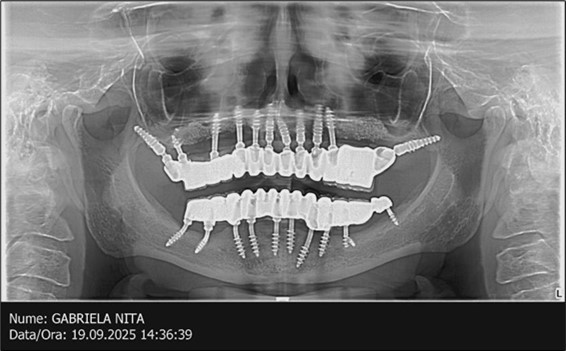

Figure 14.Rx panoramic final situation control: (a) Panoramic X-ray with the addition of a distal BCS implant in quadrant 3 at 11.2022; (b) Control X-ray, 10.2023.

The results of rehabilitation treatment with corticobasal and compressive implants with a polished surface after the failure of two stage implants were highlighted over a period of 3 years and 3 months as being very good (Figure 14, Figure 15), with the patient completing a satisfaction survey in this regard. Certainly, it is necessary to continuemonitoring these results in the long term.